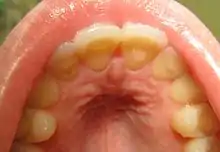

Loss of enamel (acid erosion) from the inside of the upper front teeth as a result of bulimia

The erosion on the lower teeth was caused by bulimia. For comparison, the upper teeth were restored with porcelain veneers.[13]

People with bulimia are at a higher risk to have an affective disorder, such as depression or general anxiety disorder. One study found 70% had depression at some time in their lives (as opposed to 26% for adult females in the general population), rising to 88% for all affective disorders combined.[27] Another study in the Journal of Affective Disorders found that of the population of patients that were diagnosed with an eating disorder according to the DSM-V guidelines about 27% also suffered from bipolar disorder. Within this article, the majority of the patients were diagnosed with bulimia nervosa, the second most common condition reported was binge-eating disorder.[28] Some individuals with anorexia nervosa exhibit episodes of bulimic tendencies through purging (either through self-induced vomiting or laxatives) as a way to quickly remove food in their system.[29] There may be an increased risk for diabetes mellitus type 2.[30] Bulimia also has negative effects on a person's teeth due to the acid passed through the mouth from frequent vomiting causing acid erosion, mainly on the posterior dental surface.